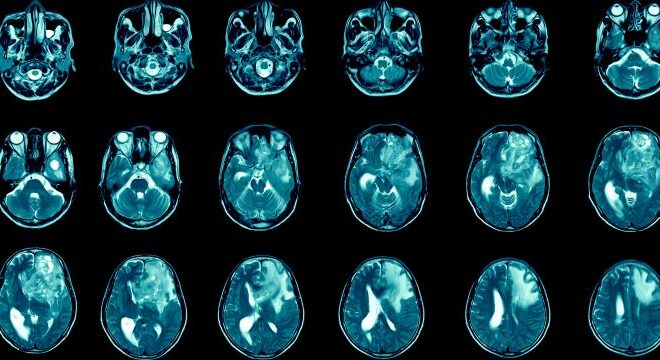

Key Insights into Glioblastoma and Its Management